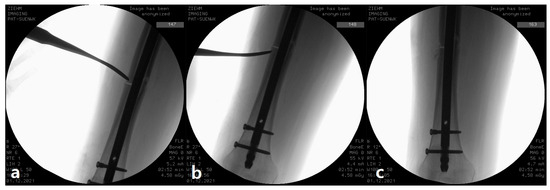

Decortication in the Surgical Management of Complete Atypical Femoral Fractures: A Strategy to Accelerate Fracture Healing

by Young-Ho Cho, Changhun Lim and Dongha Kim

J. Clin. Med. 2026, 15(2), 436; https://doi.org/10.3390/jcm15020436 - 6 Jan 2026

Abstract

Background/Objectives: Surgical management of atypical femoral fractures (AFFs) stabilized with intramedullary (IM) nailing is frequently challenged by delayed union or nonunion due to the severely suppressed bone turnover characteristic of bisphosphonate-related bone pathology, often leading to a hypertrophic nonunion-like state at the fracture [...] Read more.

Background/Objectives: Surgical management of atypical femoral fractures (AFFs) stabilized with intramedullary (IM) nailing is frequently challenged by delayed union or nonunion due to the severely suppressed bone turnover characteristic of bisphosphonate-related bone pathology, often leading to a hypertrophic nonunion-like state at the fracture site. This consecutive case series aimed to evaluate the effectiveness of intraoperative percutaneous decortication at the hypertrophic cortex in promoting rapid bone healing in complete AFFs. Methods: This was a single-center consecutive case series of patients with complete atypical femoral fractures (AFFs) treated with intramedullary nailing and adjunctive percutaneous decortication since February 2021. The standardized surgical protocol—including percutaneous decortication performed through a small anterolateral incision using an osteotome to create bone chips and stimulate the sclerotic cortex—was applied prospectively to all consecutive patients from February 2021. Of the 20 patients who underwent surgery during this period, 14 with sufficient radiographic follow-up were included in the final retrospective analysis. Data collected included patient demographics, duration of bisphosphonate use, fracture location (diaphyseal vs. subtrochanteric), operative details (including iatrogenic fracture), and radiographic bone union time. Bone union was assessed on serial radiographs by two independent observers. Results: All 14 patients were female, with a median age of 75 years (IQR 67–79 years). Thirteen patients (92.9%) had prior bisphosphonate exposure for a median of 4.5 years (IQR 3–10 years). Six fractures were subtrochanteric fractures, and six were complicated by iatrogenic fracture during nail insertion. Postoperative teriparatide was administered to six patients. Radiographic bone union was achieved in all 14 patients at a median of 19 weeks (IQR 16–22 weeks; range 16–24 weeks). No major complications (infection, implant failure, nonunion, or neurovascular injury) occurred during follow-up. Conclusions: Percutaneous decortication is a simple, safe, and biologically plausible adjunct to intramedullary nailing. In this series of 14 elderly women with long-term bisphosphonate exposure (median 4.5 years), the technique was associated with 100% radiographic union at a median of 19 weeks without major complications, suggesting a promising strategy that warrants validation in larger, controlled trials. Full article

(This article belongs to the Special Issue Accelerating Fracture Healing: Clinical Diagnosis and Treatment)

Show Figures